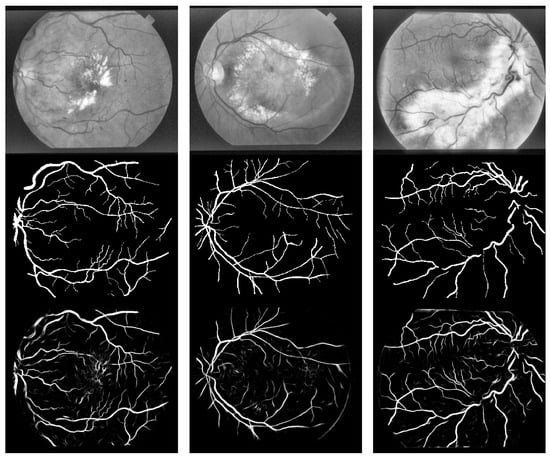

Figure 10 shows partial retinal vessel segmentation results on the DRIVE dataset. The first column displays the input images. The second column presents the segmentation results of our method, the third column shows results based on U-Net++, and the fourth column illustrates results from the DeepLab method. From Figure 10, it is evident that our semi-supervised vessel segmentation method achieves superior vessel segmentation, particularly in distinguishing thin vessels, compared to the classical fully supervised U-Net++ method. This improvement arises from the adoption of a pseudo-label filtering training strategy, which avoids generating low-quality pseudo-labels during model training. Additionally, the slicing operation expands the training samples, enabling the network to accurately identify fine vessels.

Figure 11 presents partial retinal vessel segmentation results on the STARE dataset. The first column displays the input images. The second column presents the segmentation results of our method, the third column shows results based on U-Net++, and the fourth column illustrates results from the DeepLab method. As shown in Figure 11, our method and the fully supervised U-Net++ method produce comparable segmentation outcomes, both effectively segmenting vessels correctly.

Figure 10. Segmentation result based on DRIVE dataset.

Symmetry 17 01462 g010

Figure 11. Segmentation result based on STARE dataset.

Symmetry 17 01462 g011